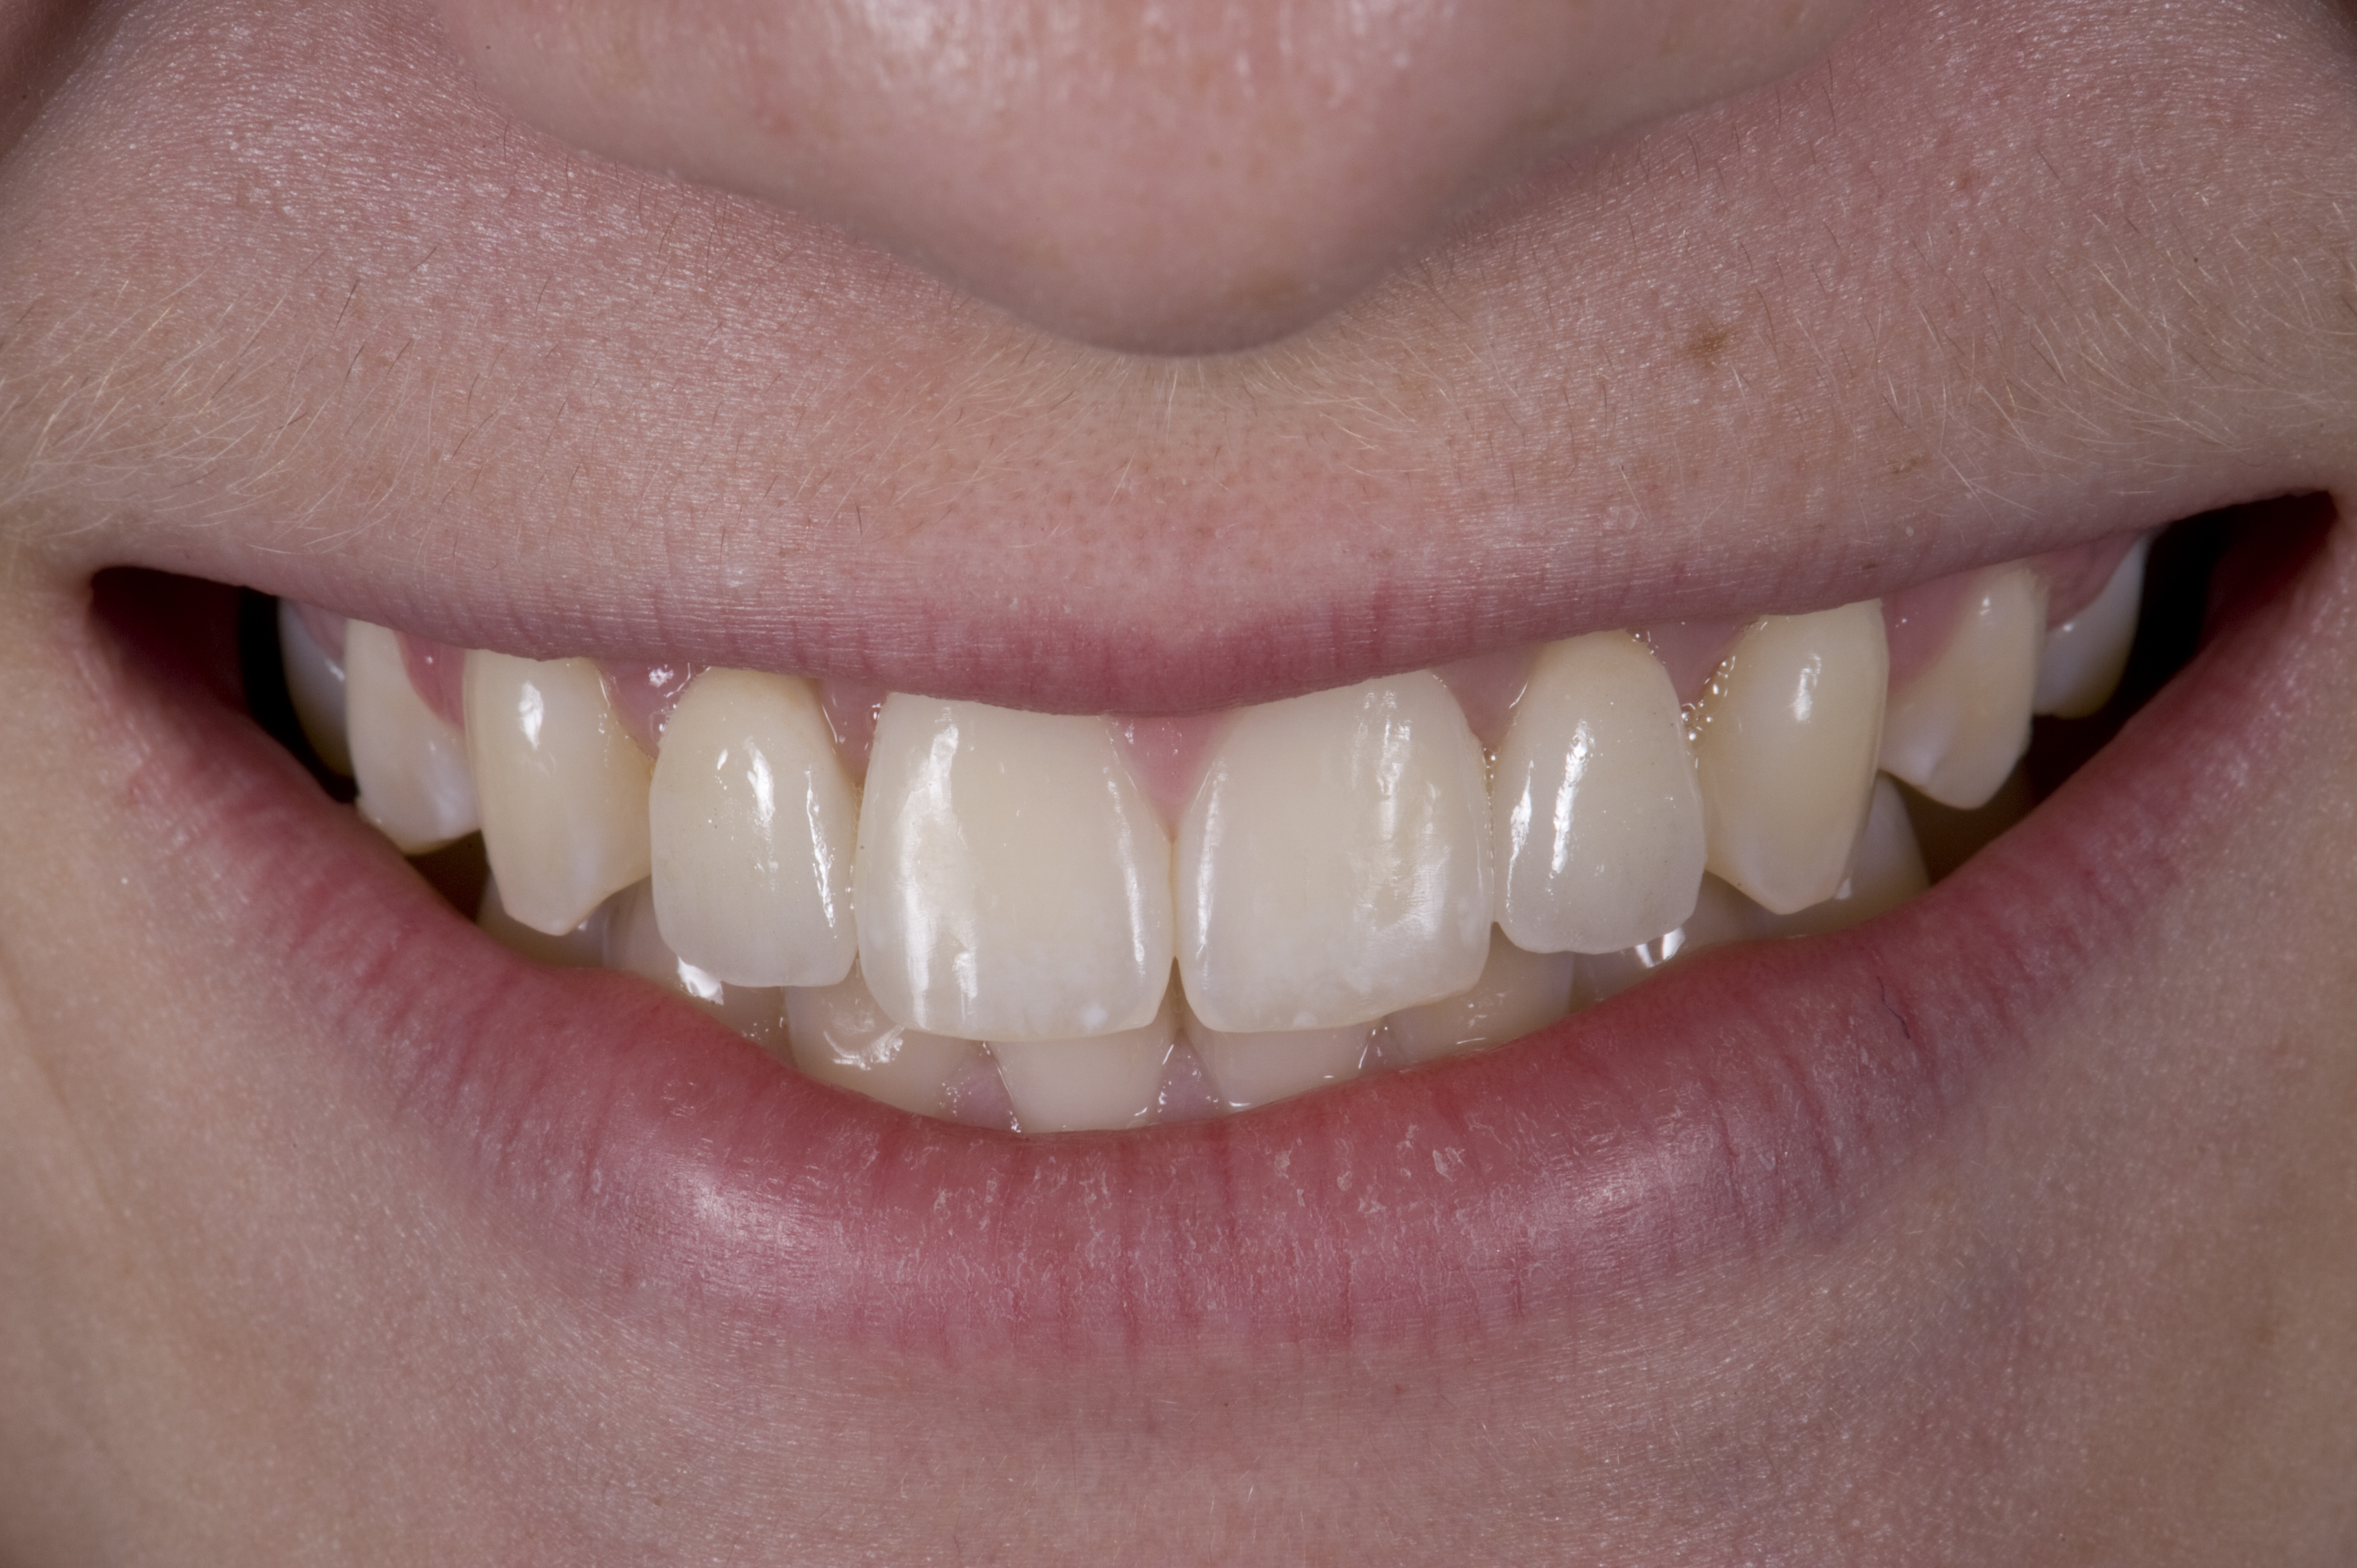

(1.) Initial presentation. Note midline shift to right, missing right lateral incisor, and diminutive left lateral incisor in crossbite.

Figure 1

A 14-year-old patient presented to the office with his mother (Figure 1). His chief complaint involved the large spaces between the teeth created by his missing right maxillary lateral incisor and his small left maxillary lateral incisor. He desired to replace the missing tooth with an implant and create a beautiful smile. Upon examination, he was found to have a class I canine and molar relationship, but because he had a tooth size/arch size discrepancy and space distal to the right central incisor, the remaining incisors had drifted to the right. The left maxillary lateral incisor was peg-shaped and in a cross bite position. Studies have shown a clear association between congenitally missing teeth and reduced tooth size.59-62 Because he was only 14 years old at the time and could not have implants placed until the cessation of growth (somewhere in the vicinity of 22 years old), he was sent to the orthodontist for alignment of the teeth.16,17 After 2 years of orthodontics, the appliances were removed, and his tooth coloration was improved using carbamide peroxide bleaching (Figure 2). Because some form of provisional needed to be placed until he was finished growing, a double-wing metal resin-bonded bridge was chosen. As discussed earlier, this is the ideal transitional prosthesis for patients that have congenitally missing maxillary lateral incisors. The benefits of this type of prosthesis include its ability to be removed and rebonded during the surgical phase of treatment and its ability to retain the roots in their proper position after orthodontic treatment.16 The final plan for the patient was to increase the width of the central and the maxillary left lateral incisor, utilizing porcelain laminate veneers to achieve the appropriate width/length ratio of 80%. A wax-up was created to idealize tooth size, a putty matrix was made from the wax-up to facilitate bonding of the incisors, and a non-precious, double-wing metal resin-bonded bridge was fabricated for lateral incisor replacement. Once the teeth were bonded to ideal size, the “Maryland Bridge” was fabricated from a polyvinyl arch impression with the newly bonded teeth (Figure 3). The metal frame was cast from a non-precious alloy to allow for fabrication of a very thin frame and to create a better surface for bonding. After sandblasting the internal aspect of the frame with CoJet™ silica (3M ESPE), accomplishing salinization, and executing cementation with a dual-cure resin cement, a fairly good adhesion to the frame was anticipated.29 The enamel surface was etched with phosphoric acid for 30 seconds, the primer (Single Bond Plus, 3M ESPE) was applied to both the internal surface of the sandblasted framework and the etched enamel, and the bridge was cemented with RelyX™ ARC (3M Espe) dual-cured resin cement (Figure 4 and Figure 5).